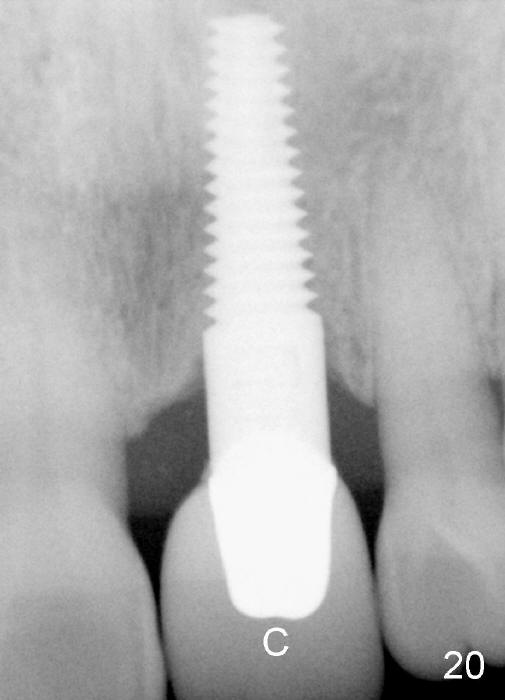

A 60-year-old lady had an abscess mesial to #9 six years ago (Fig.1,2 <), treated as a perio lesion by laser (Fig.3) and osseous surgery without bone graft (Fig.6, followed by CT exam revealing semi-circumferential bone loss (Fig.4,5). When the perio treatment failed, attention was paid to endo aspect (Fig.7-9). In fact the pulp was found to be vital when access to root canal therapy was made. As expected, the treatment failed again. The palatal fistula persisted. The infection was suspected to be a source of remote immediate implant site (#30). The tooth #9 was extracted. It appears that there is a semilunar crack line in the linguomesial root (Fig.12). When the socket healed 2 weeks post extraction (Fig.10), the #30 buccal defect was debrided with bone graft. There was no bone resorption 4 weeks post extraction (Fig.11); a 4.5x17 mm implant was placed (Fig.13-15). An immediate provisional was fabricated (Fig.16-18). Fig.19,20 were taken 3 months post implantation and 7 months post cementation, respectively. Dense bone forms around the implant coronally 4 years 5 months post cementation (Fig.21), while the gingiva is healthy palatally (Fig.22) and buccally (Fig.23).